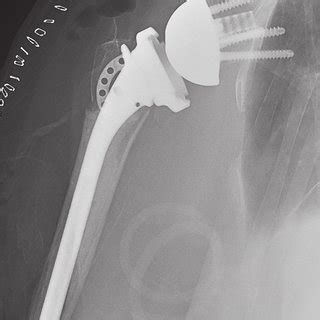

The four parts are the humeral head, the greater tuberosity, the lesser tuberosity and the humeral shaft. To determine the effect of alternate devices in the management of four part proximal humerus fractures in patients on the risks of reoperation, need for implant.

Read the classification, causes, symptoms, treatment, exercises. Typically, the most common cause of proximal humerus fractures. Read the classification, causes, symptoms, treatment, exercises. The treatment of proximal humeral fractures has evolved significantly over the past decade. Studies have shown associations with delayed reaction times and impaired neuromuscular protective forces. Unfortunately, proximal humerus fractures are often serious injuries, especially when the alignment of the bone has shifted significantly. Approximately 80% of all proximal humeral. Gr tuberosity avulsion a2 type 1: A proximal humerus fracture is a break of the upper part of the bone of the arm (humerus).3 symptoms include pain, swelling, and a decreased ability to move the shoulder.1 complications may include axillary nerve or axillary artery. Proximal humerus fracture malunion and nonunion. Nonoperative treatment of proximal humerus fractures. The neer system divides the proximal humerus into four parts and considers not the fracture line, but the displacement as being significant in terms of classification. Orthoflix simall free full length video! Proximal humeral fractures represent <5% of all paediatric fractures. • radiographically will see alignment between medial shaft and head segments. To determine the effect of alternate devices in the management of four part proximal humerus fractures in patients on the risks of reoperation, need for implant. The four parts are the humeral head, the greater tuberosity, the lesser tuberosity and the humeral shaft.